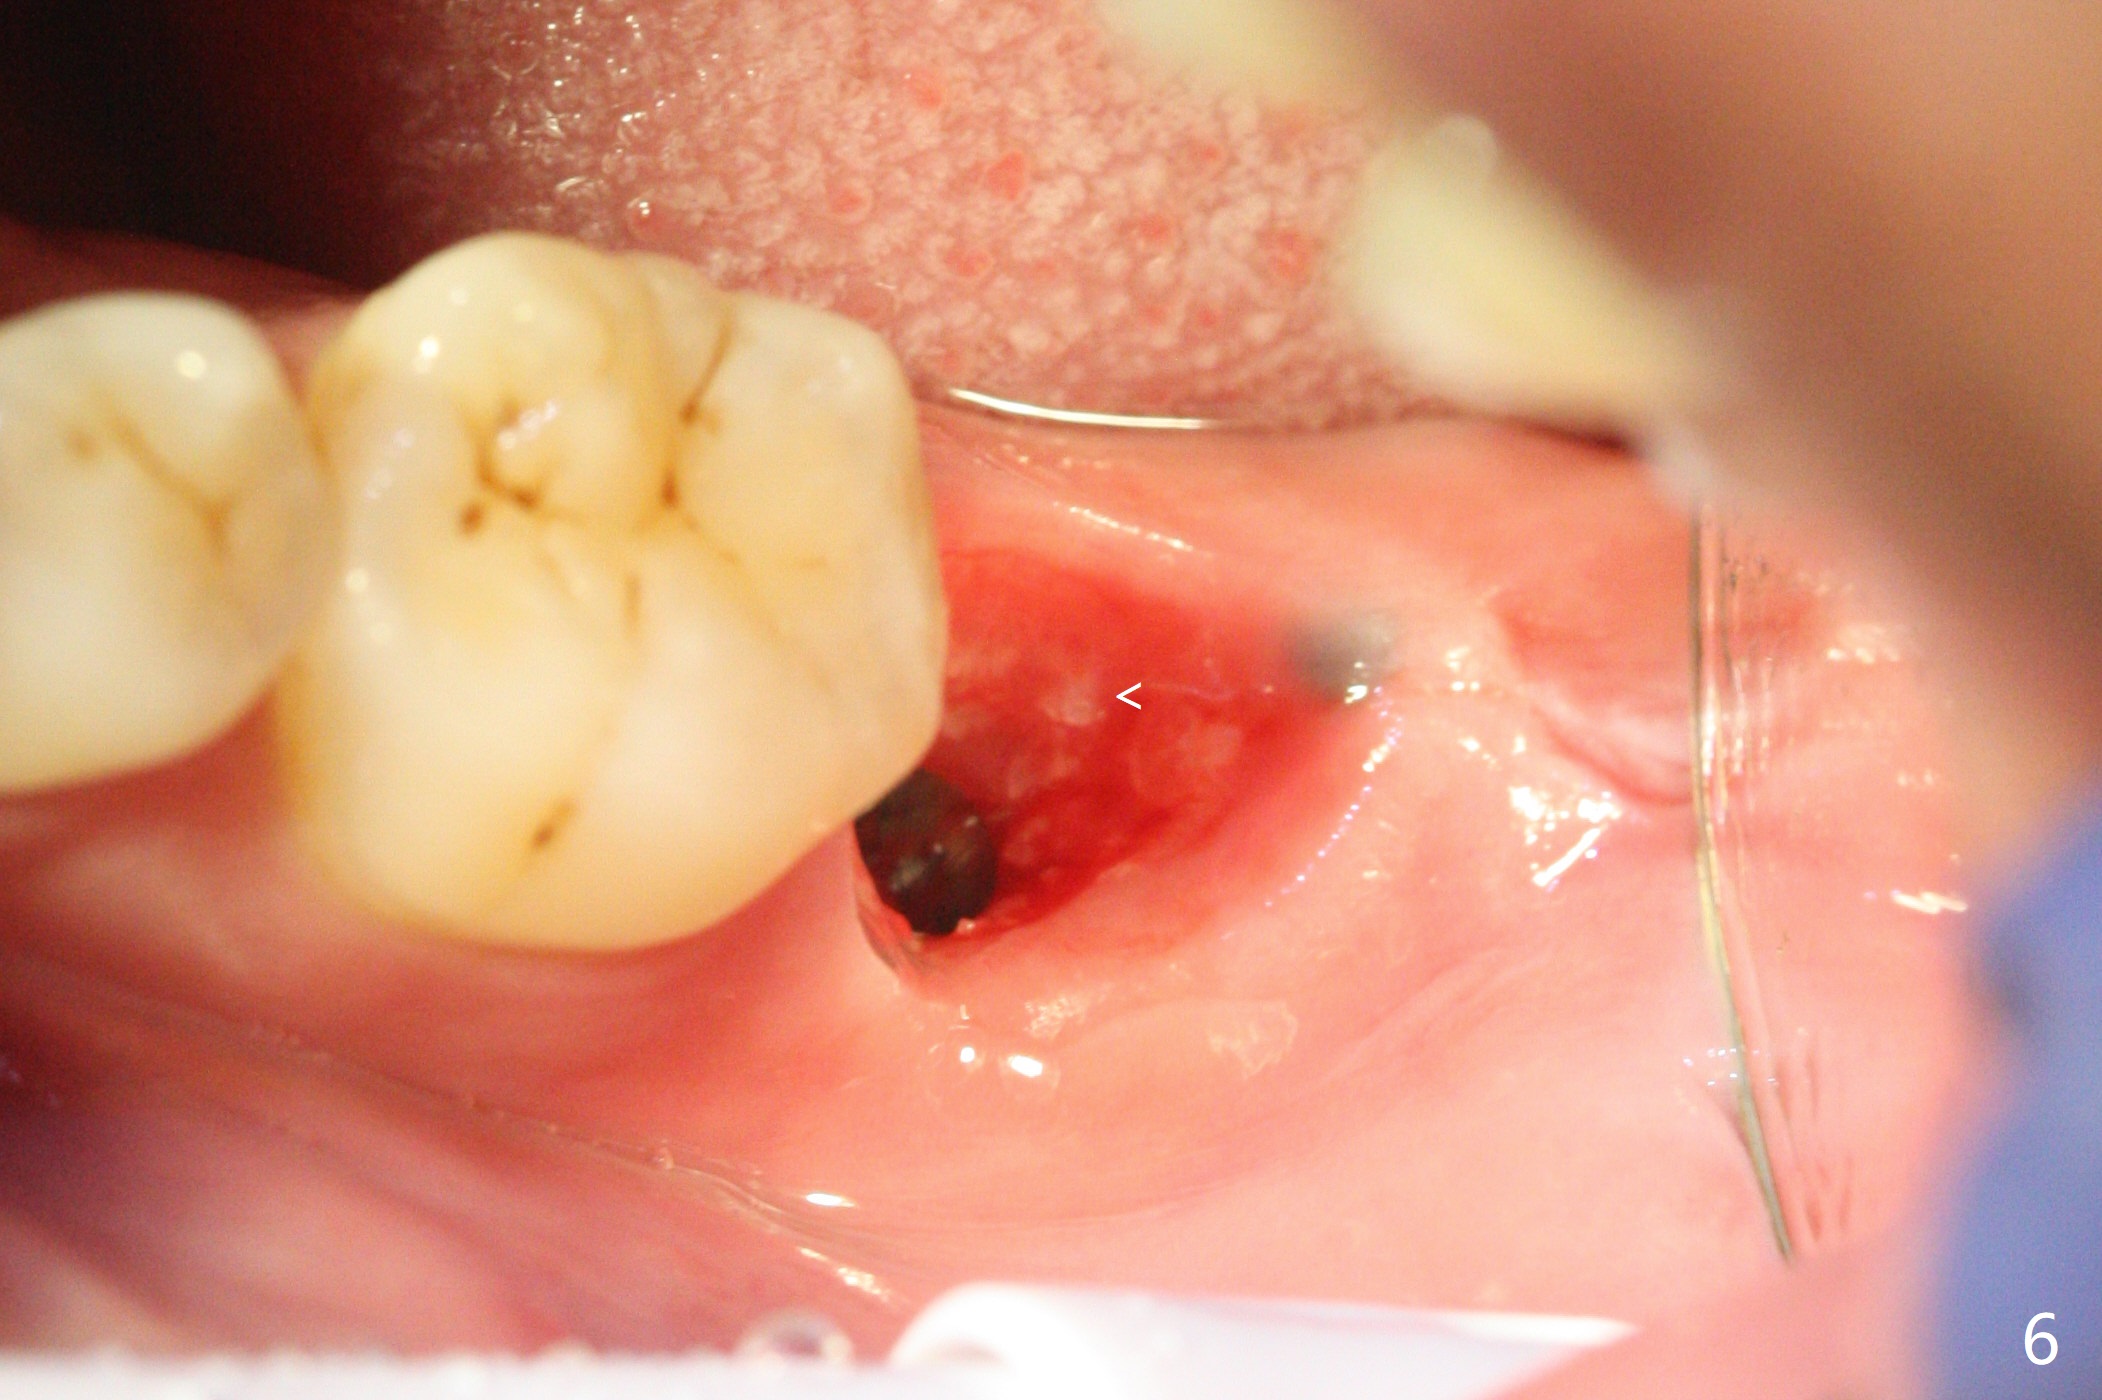

After placement of a 5x11 mm implant and cover screw at #18, allograft mixed with PRF (sticky bone) is placed in the peri-implant space, but it appears that bone density in the apical region (Fig.1 A) is lower than that in the coronal one (C) because of a constriction between the implant and the distal crest (*). Ideally the undercuts (Fig.2 *) of the extraction socket (black area) should be identified. Place bone graft in the undercuts (Fig.3 red circles) after osteotomy (white outlines) and before implant placement! A 4.5x1 mm temporary abutment is placed for an immediate provisional. The 2nd shortcoming of this case is that the implant is placed a little buccal. The papilla mesial to the immediate provisional (Fig.4 P) looks normal 4 days postop (no food impaction is expected when a final restoration is cemented). Additional acrylic (*) was placed to close a buccal gap when the provisional was seated with the temporary abutment. The patient reports loss of a piece of material in 4 days. It must be the additional acrylic, since it is absent 6 weeks postop (Fig.5). The provisional (Fig.5 P) looks wide, probably related to post-extraction gingiva and bone atrophy (Fig.6, 7 *). Bone graft (Fig.6 <) becomes a component of the gingival cuff. The provisional is re-trimmed for better oral hygiene. The gingival cuff is basically healthy 3.5 months postop, although the temporary abutment is loose and the implant is tender to rewinding and winding (Fig.8). The implant seems to remain non-osteointegrated 3.5 months postop (Fig.9). Although the bone density around the implant increases nearly 6 months postop (Fig.10), the implant remains tender when a 5x4(4) mm pair abutment is tightened. The healing abutment is reused. The bone density around the implant increases 11 months postop (Fig.11). Uncover is done with 5.5 mm profile drill. One month post uncover (12 months postop), the implant remains unstable (Fig.12). Prepare sticky bone x1. Make incision for exploration, including retightening the implant after Titanium brush and H2O2 Q-tip rubbing. If needed, a larger and shorter UF implant is a replacement (Fig.13). The implant is removed, cleaned with Titanium brushes and H2O2 in vitro and repositioned 12 months postop (Fig.14: arrow (gaps: post granulation tissue removal)). The gaps are regrafted with sticky bone and covered with PRF membrane and Cytoplast. Although the patient complains of severe pain the first 2-3 postop, the wound is apparently healing 12 days postop. The Cytoplast is exposed asymptomatic 5 weeks postop (Fig.16) and removed (Fig.17). The wound appears to have healed without loss of the bone graft (Fig.18).术后四个月伤口愈合,骨粉几乎没有丢失,有骨小梁形态(图十九:*)。切开,刮匙去骨,有一定硬度,即刻放置修复基台,完全就位(图二十),制备临时牙冠,牙周敷料固定组织瓣(没有缝线)。